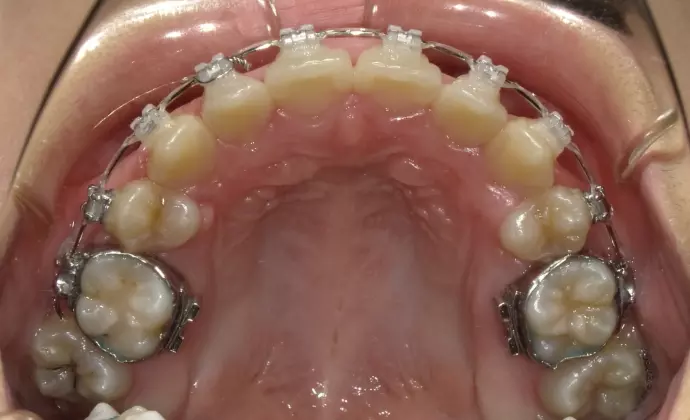

このケースは前歯がデコボコしていて八重歯になっています。中間の歯を抜歯して治療した例です(12歳 女児)

| 装置 | 歯の表側にブラケット装置 |

| 抜歯部位 | 上下の左右第一小臼歯 |